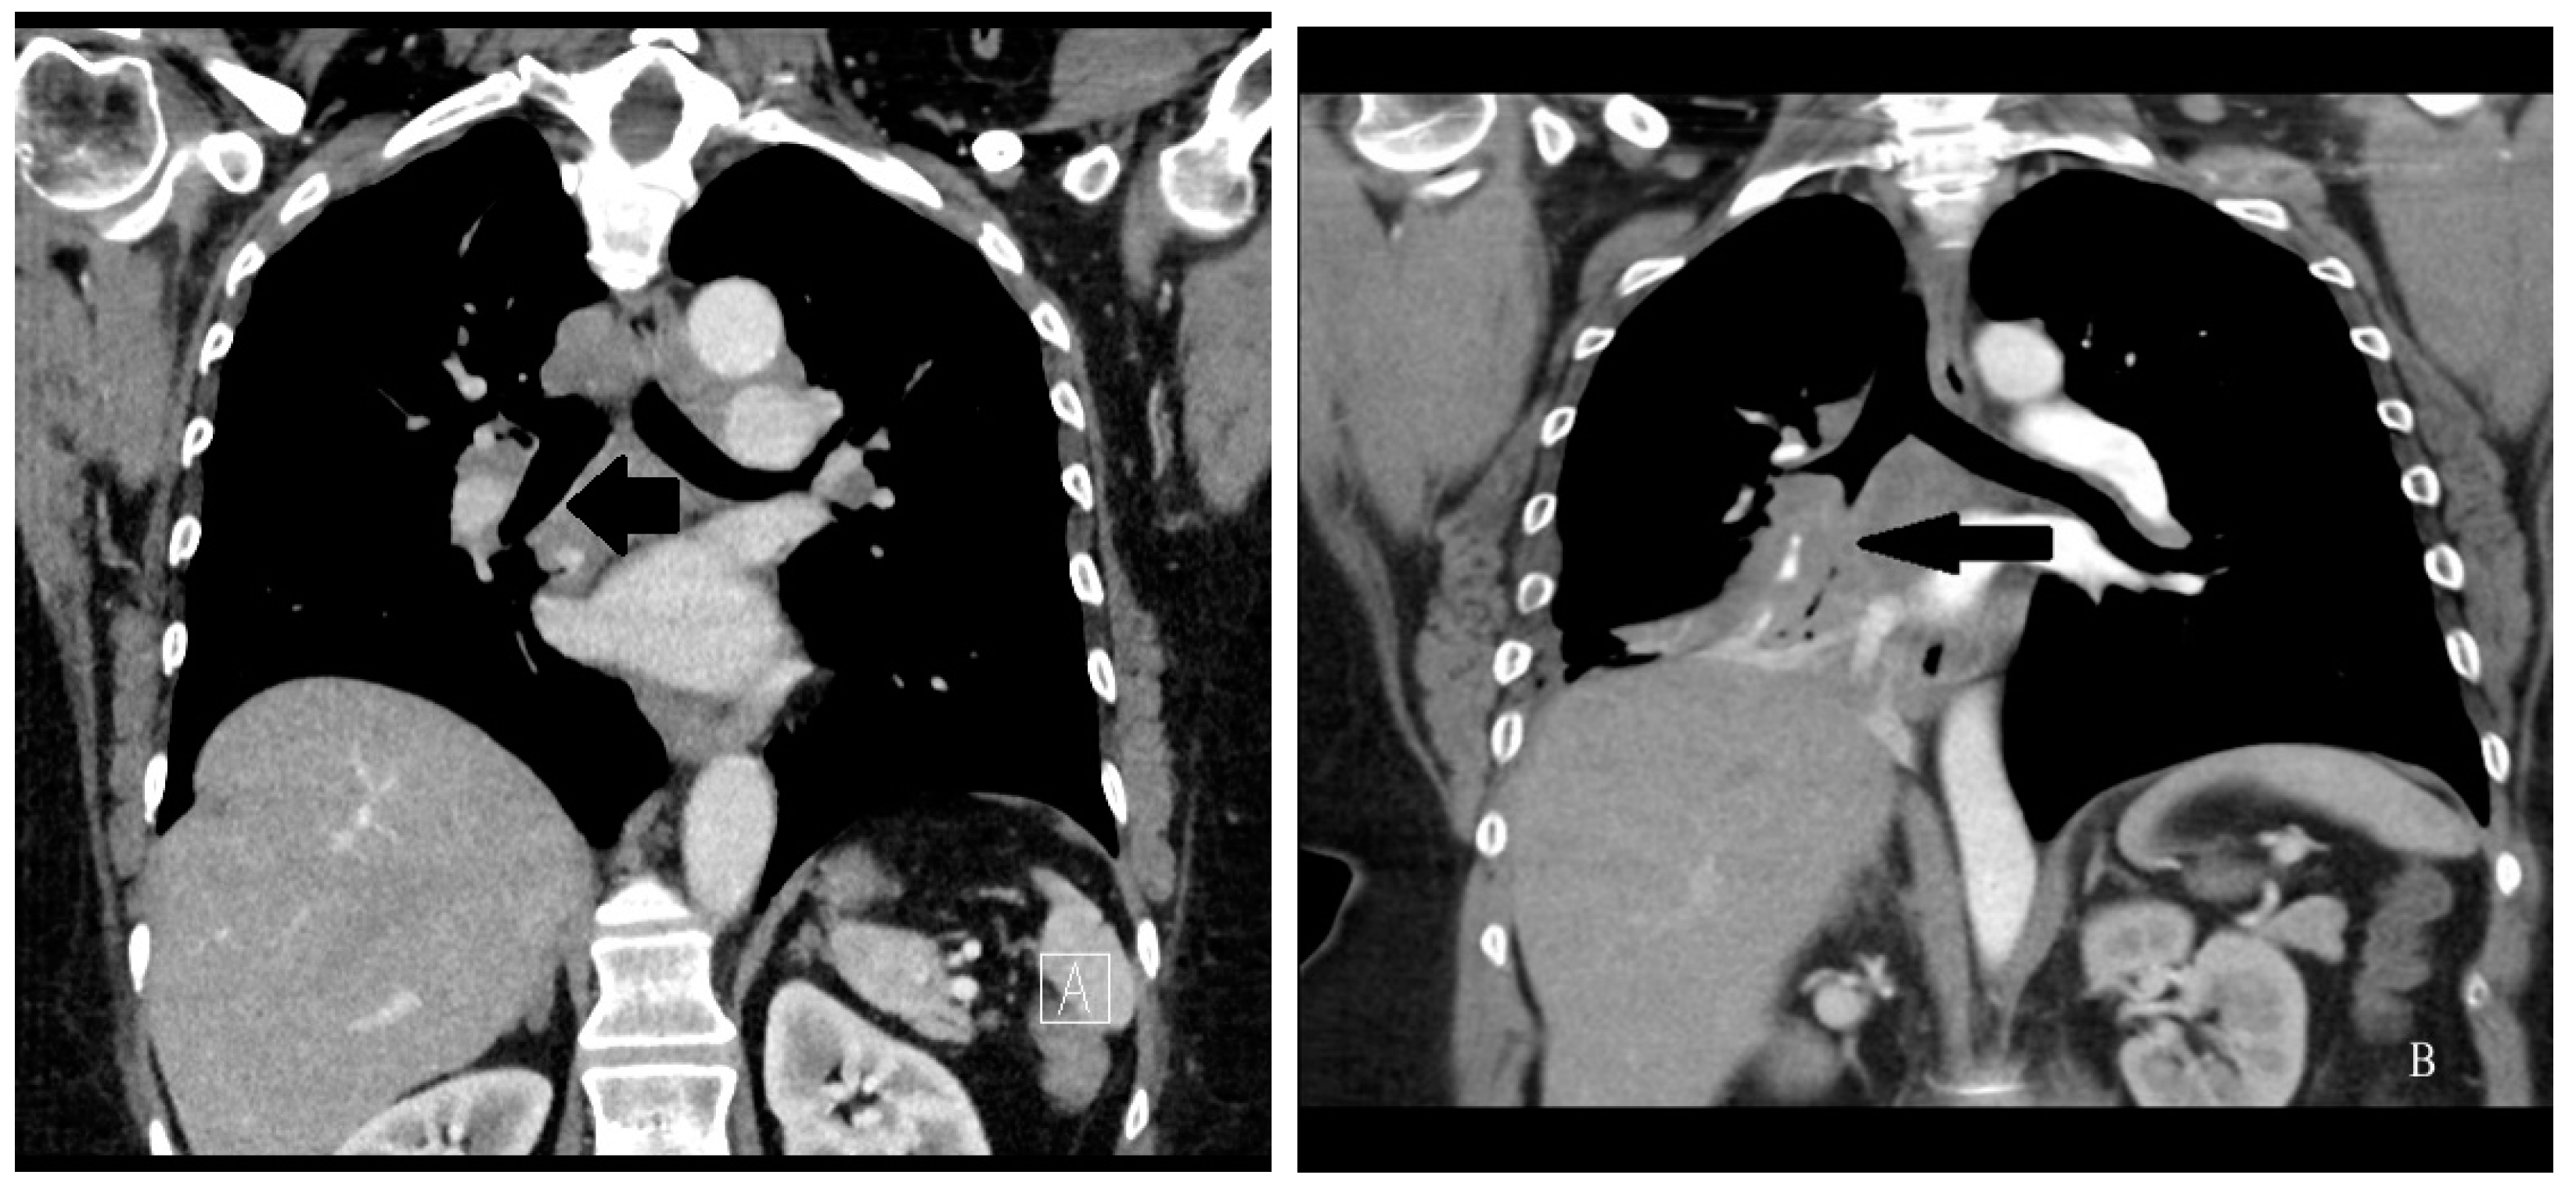

Figure 3.

Chest CT scan image of a patient with pulmonary sarcoidosis demonstrating lung opacities from granulomatous inflammation around pulmonary vessels (thin arrows). Scatter parenchymal nodules and hilar adenopathy are seen, especially on the right (thick arrow).